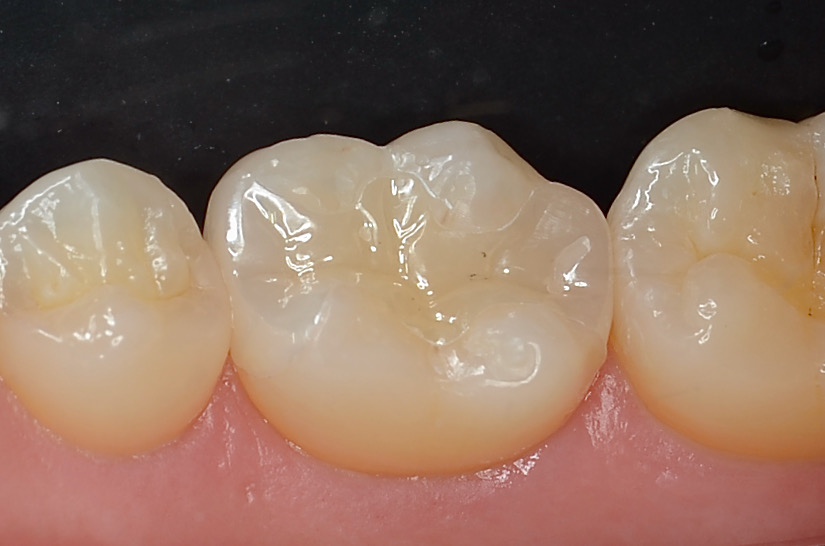

研磨終了

噛み合わせの調整をした後に、」段差の部分をしつこく研磨します。 -

-